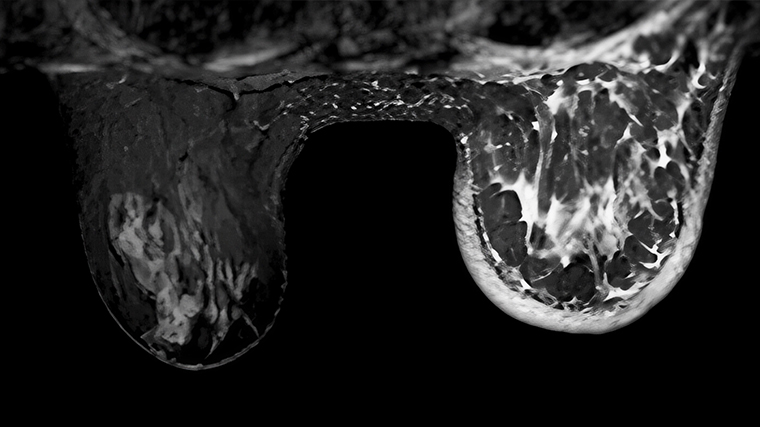

Часто рак молочной железы относится к категории аденокарцином — опухолей из железистого эпителия. Они развиваются внутри протоков молочных желез, постепенно разрастаясь и захватывая все большее количество тканей.